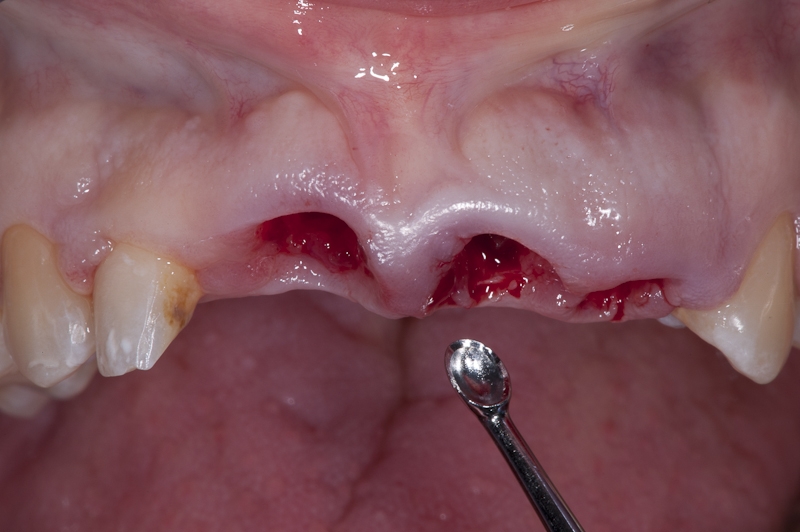

Socket preservation with permamem® - Dr. R. Rannula

Situation after tooth extraction.